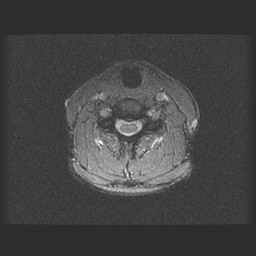

Centrale Wervel Zuil